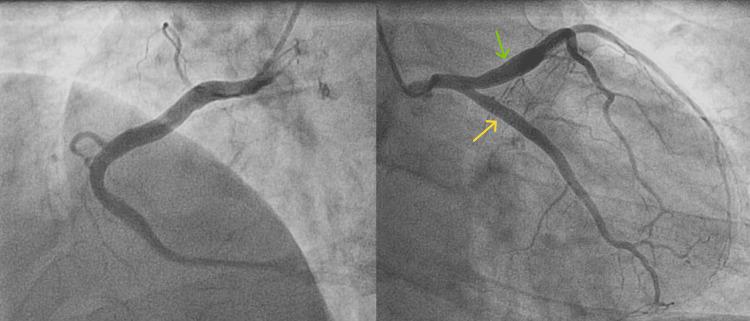

Coronary artery ectasia (CAE) is a rare condition, affecting 3%-8% of patients with atherosclerotic coronary artery disease, and is characterized by the abnormal dilatation of the coronary arteries. While the etiology of coronary artery ectasia encompasses a myriad of acquired and genetic factors, its pathogenesis still remains a subject of investigation. The clinical manifestations are varied, ranging from asymptomatic cases to chest angina and myocardial infarction. Coronary angiography remains the gold standard for diagnosing CAE. We herein report four cases of coronary ectasia: the first involving myocardial infarction, the second associated with bicuspid aortic valve with severe aortic regurgitation, the third detected during coronary angiography for moderate left ventricular dysfunction, and the last one detected during coronary angiography for stable angina. The aims of our study are to highlight the diversity of clinical presentations as well as the challenge of management, given that there are no universal treatments or guidelines.

冠状动脉扩张(CAE)是一种罕见病症,在动脉粥样硬化性冠状动脉疾病患者中占3%-8%,其特征为冠状动脉异常扩张。虽然冠状动脉扩张的病因包括众多后天因素和遗传因素,但其发病机制仍是一个研究课题。临床表现多样,从无症状病例到心绞痛和心肌梗死不等。冠状动脉造影仍然是诊断CAE的金标准。我们在此报告4例冠状动脉扩张病例:第一例伴有心肌梗死,第二例与二叶式主动脉瓣伴严重主动脉瓣反流相关,第三例在冠状动脉造影时因中度左心室功能障碍被检测出,最后一例在冠状动脉造影时因稳定型心绞痛被检测出。鉴于目前尚无通用的治疗方法或指南,我们研究的目的是强调临床表现的多样性以及管理方面的挑战。